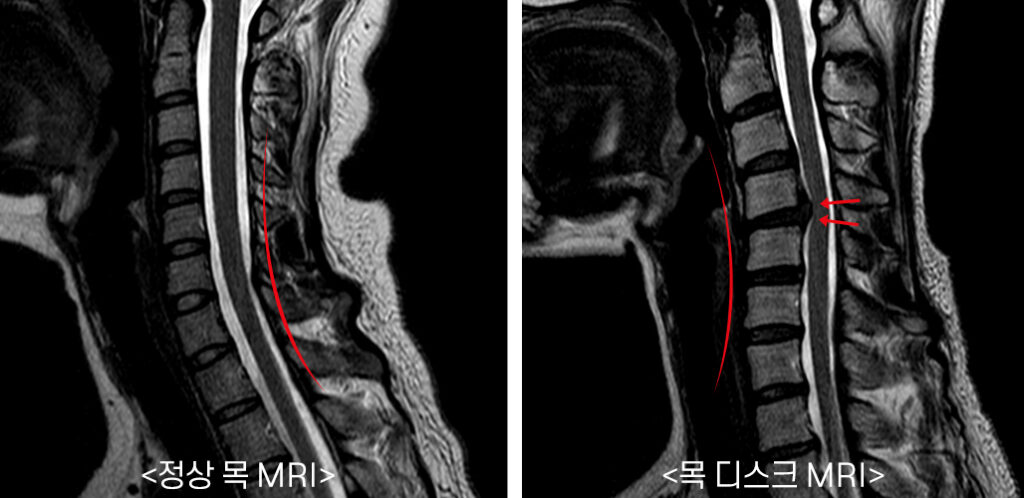

목은 목뼈(경추) 7개로 되어 있다며 뼈와 뼈 사이에 디스크가 있습니다. 디스크는 기립 자세에서 수직으로 끼치는 압력을 분산하고 목이 동작할 때 관절 역할을 합니다. 나이가 들면 아무라도 피부 탄력이 감퇴하여 주름이 생기듯 척추의 디스크도 수분 함유하고 있는 분량이 쇠퇴하여 긴장되고 이로 인하여 충격을 섭식하고 압력을 분산시켜서하는 기능이 저하되요.

목디스크는 왜 생기는 걸까요? 사람들이 나이가 들면 디스크의 수분 성분인 수핵의 수분함유 분량이 떨어뜨리여 탄력이 감소하게 되고 해로운 자세나 사고 등의 바깥 부분적인 자극에 의해 디스크가 밀려나 목디스크 질환의 이유가 되는 것이 된다고 합니다. 평범할 때 생활하면서 틀린 습관, 목에 가해진 충격 등에 의해 일어나기 쉽다고 하고요.